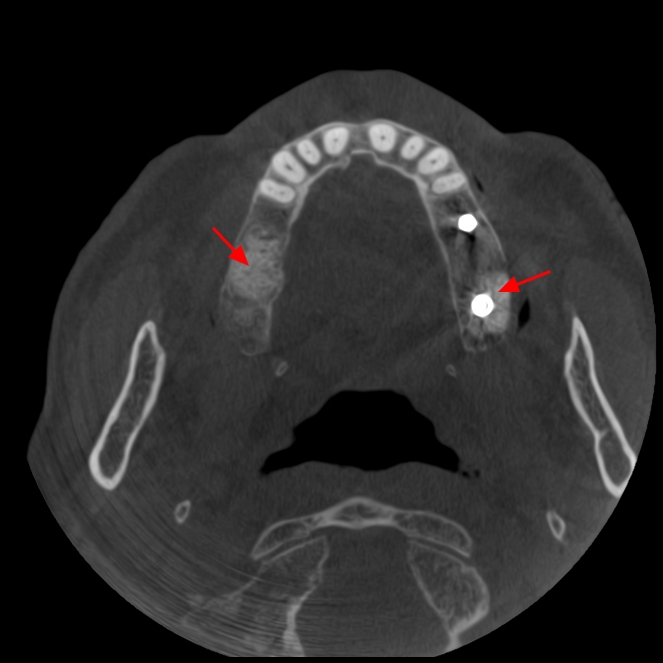

En este contexto, la tomografía computarizada de haz cónico (CBCT) se ha convertido en una herramienta esencial para los profesionales de la odontología. Gracias a la radiología 3D, los especialistas pueden evaluar con exactitud el volumen óseo disponible, identificar estructuras anatómicas importantes (como el nervio dentario o el seno maxilar) y diseñar el tratamiento con la máxima previsión y seguridad.

Para el paciente, esto se traduce en procedimientos más seguros, menos invasivos y con resultados más predecibles. En la fase de seguimiento, el CBCT también permite comprobar la correcta integración del injerto óseo y la evolución del tejido antes de colocar el implante definitivo.